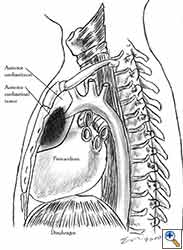

Pericardial reconstruction is indicated after extrapleural pneumonectomy for diffuse malignant pleural mesothelioma. Right-sided pericardioplasty is performed to prevent cardiac dislocation as discussed above. Left sided pericardial defects that result after extrapleural pneumonectomies are large and there is no risk of cardiac strangulation, but reconstruction is recommended in order to prevent constrictive epicarditis (Figure 3) [4].

Video 1 depicts a pericardial reconstruction with Marlex after a right completion pneumonectomy with pericardiectomy for lung adenocarcinoma (see also Figure 1). The technique of pericardial reconstruction after the resection of invasive mediastinal tumours is illustrated in Figures 8a-c). Video 2 depicts a pericardial reconstruction with Mersilene mesh after the resection of a malignant thymoma invading the anterior pericardium (see also Figure 4b). The technique of right pericardial reconstruction after extrapleural pneumonectomy is illustrated in Figures 9a and 9b). Video 3 depicts a pericardial reconstruction using Gore-Tex Dual Mesh after a left extrapleural pneumonectomy (see also Figure 3). Care must be taken to prevent constriction (Figure 10).